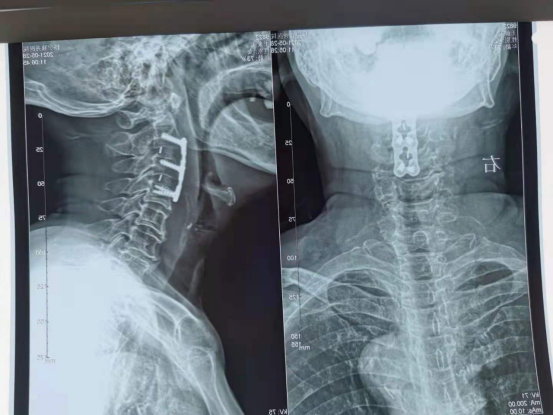

怀宁独秀医院骨二科近日完成一例高难度的高位颈椎病手术。患者王某,女性,73岁,四肢麻木、乏力伴步态不稳多年并进行性加重,逐渐出现手部握力减退,不能持物,行走困难伴踏棉感来我院求治。核磁共振检查提示:颈2-3、3-4椎间盘脱出,椎管狭窄,颈髓变形,颈椎退变,诊断为“脊髓型颈椎病”。在“经鼻气管插管静吸复合麻醉”下,成功实施了“经前路颈2-3、3-4椎间盘摘除,椎管减压+椎间植骨融合+内固定术”,手术顺利完成。此手术切口长仅3厘米,手术时长仅70分钟。目前病人恢复良好。

术后X光片